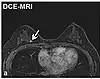

| Dynamic contrast enhanced | DCE | Measures changes over time in the shortening of the spin–lattice relaxation (T1) induced by a gadolinium contrast bolus.[27] | Faster Gd contrast uptake along with other features is suggestive of malignancy (pictured).[28] | ![]() | |

Perfusion weighted

- Dynamic contrast enhanced (DCE): Measuring shortening of the spin–lattice relaxation (T1) induced by a gadolinium contrast bolus.[46]

The acquired data is then postprocessed to obtain perfusion maps with different parameters, such as BV (blood volume), BF (blood flow), MTT (mean transit time) and TTP (time to peak).